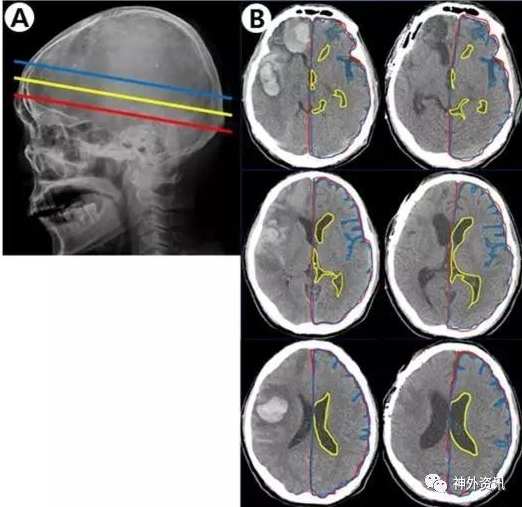

該研究收集作者所在單位2011年至2015年接受手術(shù)治療的自發(fā)性腦出血患者。研究對象的血腫位于幕上單側(cè)大腦半球;根據(jù)術(shù)前和術(shù)后3個月在頭顱CT軸位3個平面,即室間孔平面、透明隔平面和側(cè)腦室平面上的影像片(圖1)

計算發(fā)生出血對側(cè)的腦實質(zhì)面積與同側(cè)顱腔面積之比以消除個體差異,分析與對側(cè)腦組織體積變化的相關(guān)因素。

總共納入44例患者,其中12例血腫清除后骨瓣復(fù)位,15例行血腫清除加去骨瓣減壓術(shù),17例行血腫穿刺引流術(shù)。結(jié)果表明,所有患者術(shù)前與術(shù)后3個月CT圖像上,在室間孔、透明隔和側(cè)腦室3個平面的對側(cè)腦組織與同側(cè)顱腔面積平均比值,分別為92.3%比88.8%、90.3%比85.3%和86.9%比82.5%,差異均有統(tǒng)計學(xué)意義(P<0.001)。血腫破入腦室是導(dǎo)致對側(cè)腦組織體積縮小的最顯著因素(P=0.006);此外,入院時GCS評分低(P=0.016)和吸煙(0.039)也是對側(cè)腦組織體積縮小的獨立影響因素。